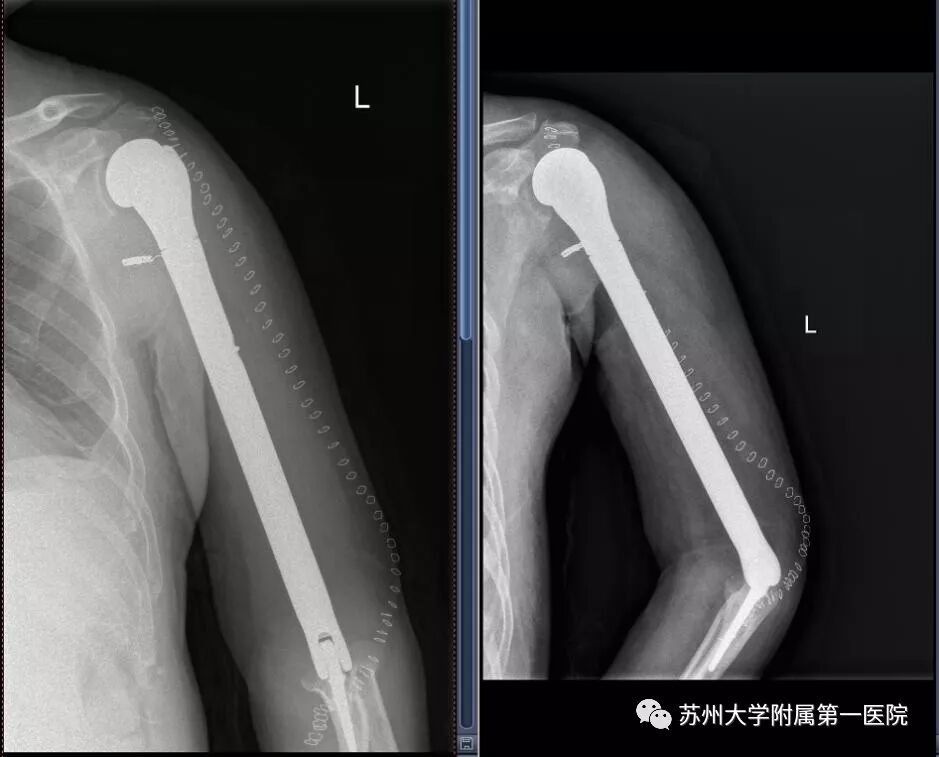

方大叔手术后3天的X线片

这是一场“穿针引线”、堪称“绣花”的高难度手术。不仅需要巧妙地绕开神经和血管,切除病灶,放置假体,而且还需要一点一点将肌腱重新搭好。

最终,在医院、科室、团队、患者和家属等多个层面的支持和努力下,在骨科杨惠林主任、黄立新主任的关心和指导下,经过一个多月的精心准备,麻醉科、手术室等多学科医护人员携手合作。历经4.5个小时后,陆俭主任团队顺利为方大叔完成了手术。

术后3天,方大叔就开始下床,慢慢进行功能锻炼。术后一周,患肢的疼痛就已经基本消失,功能也恢复了80%以上。术后VAS疼痛评分从术前的8分降到术后的2分。在大家都为手术的成功感到高兴时,陆俭主任心里却依然绷着一根弦,手术的成功只是一个重要的开始,术后的恢复如何,是否还会复发等问题依然是个未知数。